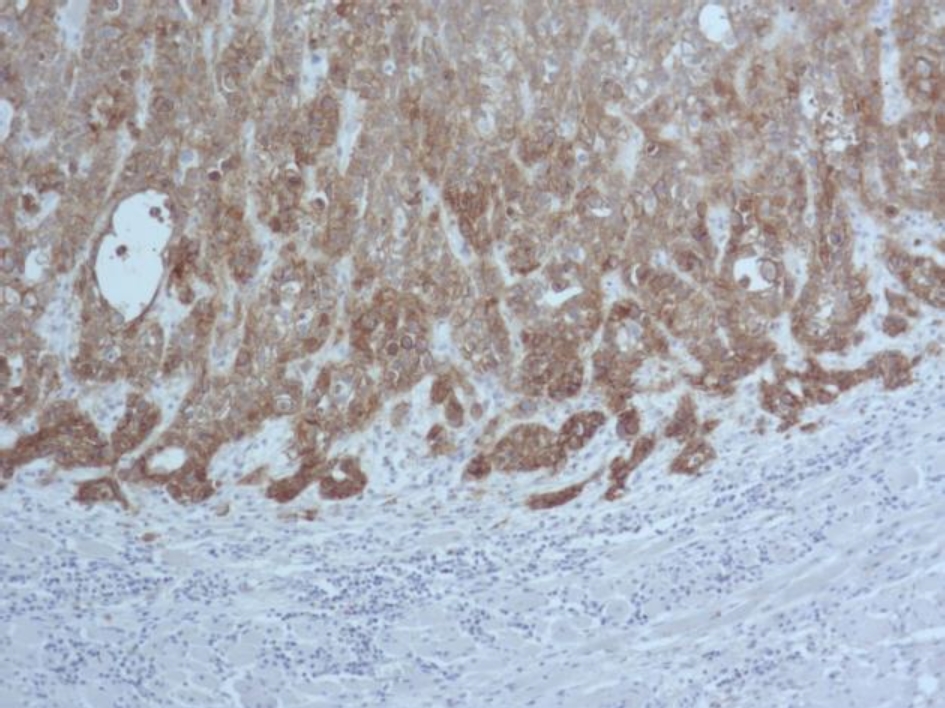

Во всех 19 исследуемых наблюдениях проведено дополнительное параллельное иммуногистохимическое исследование по выявлению экспрессии белков EGFR и Cyclin D1 соответственно, при этом диффузная, преимущественно умеренная экспрессия EGFR опреде-лялась в 17 (89 %) из 19 наблюдений (рис. 3), очаговая слабая экспрессия – в двух наблюдениях (11 %).

Рис. 3. Диффузная экспрессия EGFR в клетках плоскоклеточного рака языка. ИГХ окрашивание, ×100